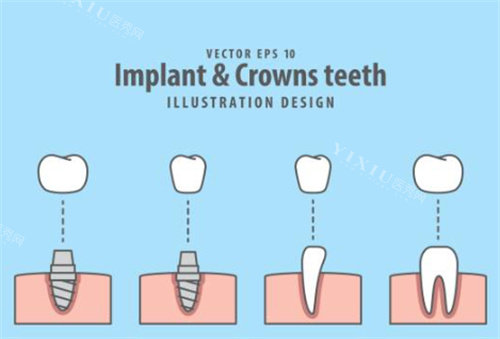

桩冠是一种修复牙体缺损的方法,主要用于修复因龋齿或外伤等原因导致的牙齿大部分缺损。其过程是先将牙齿根管内的神经和血管等去除,然后在根管内放置一个桩,再将制作好的牙冠粘接到桩上。而桩核冠是指在牙齿缺损较大,或因外伤等原因仅留残根时,先在根管内制作桩核,然后再在桩核上进行牙冠修复。简单来说,两者的关键区别在于是否需要制作桩核。

桩冠一般是直接做一个桩和冠的复合体进行修复,一步到位。而桩核冠则是先做一个桩核,此后再取模,再制作牙冠,分步骤完成修复。这种分步骤的制作方式使得桩核冠更加精细。